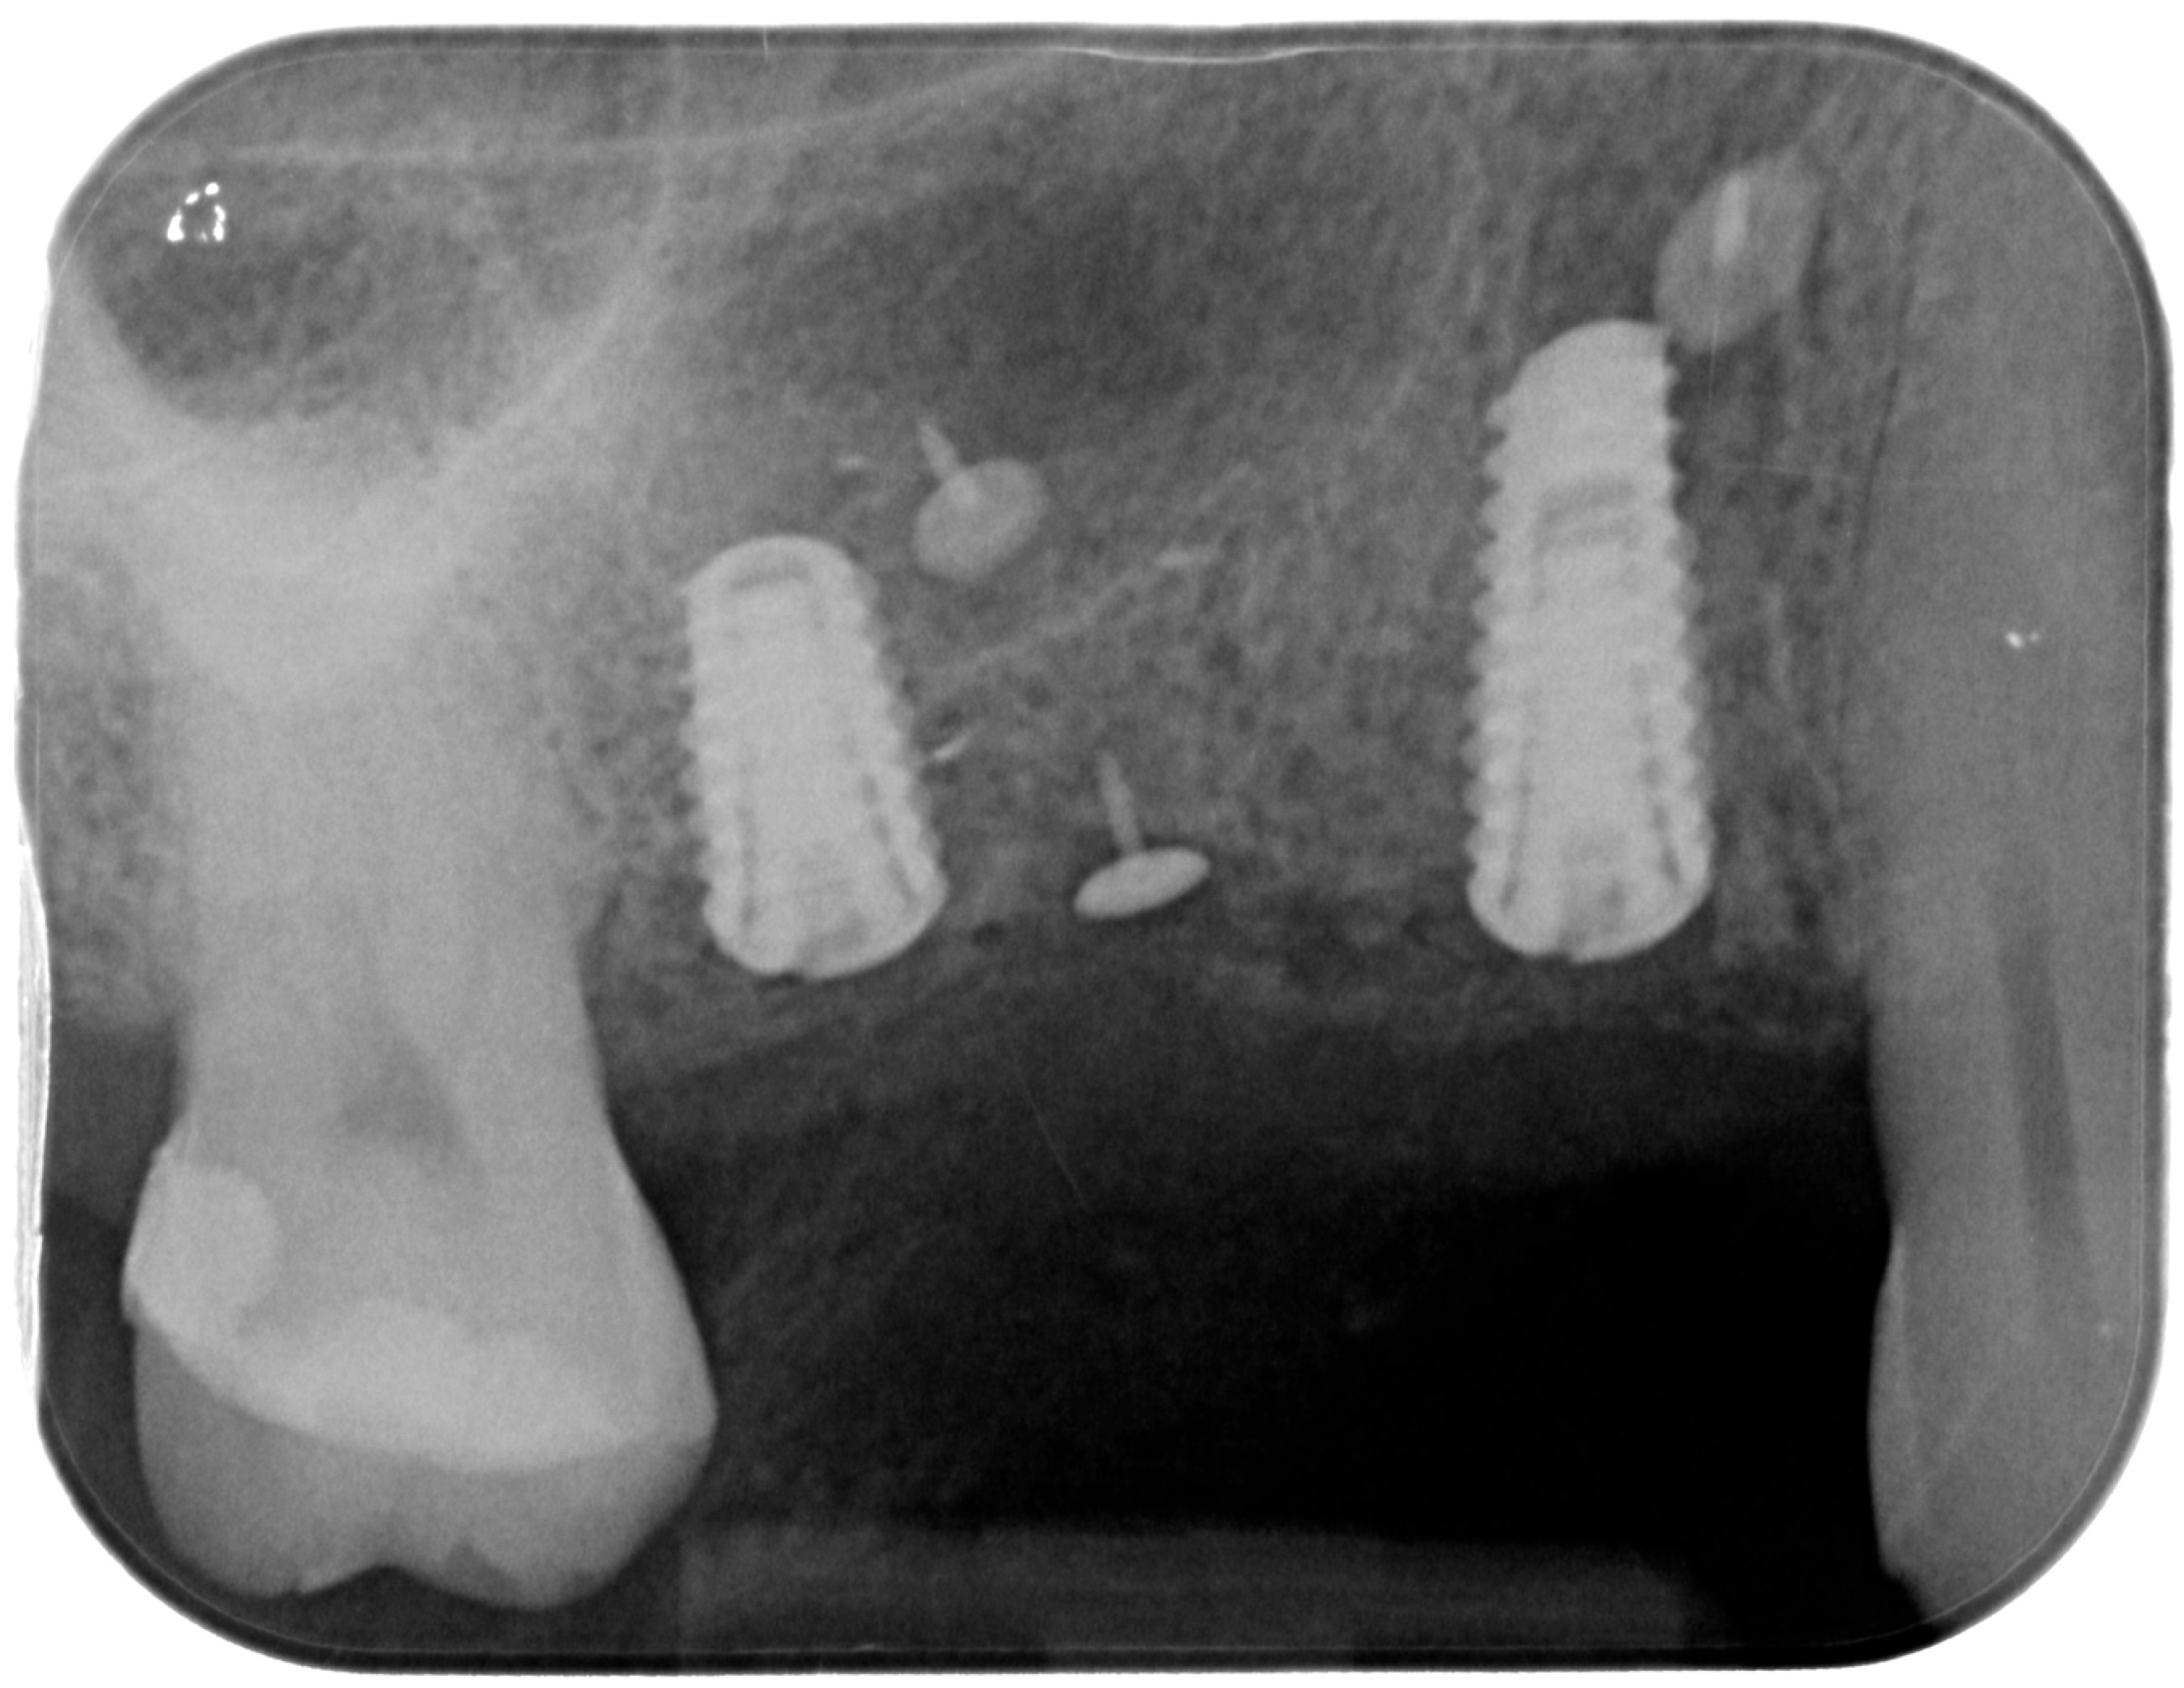

Releasing incisions were made through the periosteum at the base of the flap in order to allow tension-free adaptation of the wound margins. Horizontal mattress sutures as well as single interrupted sutures (CV-5 and CV-7, Gore-Tex; W.L. Gore & Associates, Flagstaff, AZ, USA) were placed to achieve healing by primary intention (Figure 7 and Figure 8).

Figure 8.

Postoperative intraoral X-ray.

For the evaluation of the mesial and distal MBL, intraoral digital radiographs were taken using the long-cone paralleling technique with the central beam directed to the alveolar crest. Periapical radiographs were taken at the delivery of the prosthesis and after 1 year of prosthetic loading (T2). The mesial and distal MBL, i.e., the distance between the top of the implant shoulder and the first visible bone-to-implant contact, were measured at the mesial and distal aspect with a 10–15× magnification using an image analysis programme (ImageJ v 1.49, NIH, Bethesda, MA, USA). The length of the implant was used as known measure for the calibration and determination of the exact magnification and distortion of the images. All measurements were performed by two examiners to the nearest 0.1 mm. In case of disagreement, the evaluation was re-done and results discussed until an agreement was found.